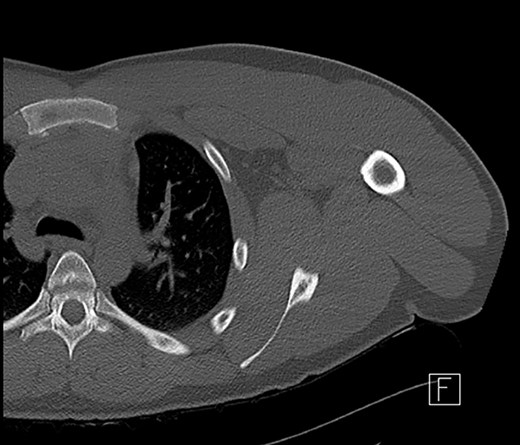

A 21-year-old man presented to the emergency department complaining of a left shoulder injury after being tackled during a game of rugby 4 days prior. His pain had gradually worsened, and he began feeling non-specifically unwell. He had no other medical history. Examination findings included significant pain and reluctance to move his shoulder with tenderness and swelling overlying his upper left pectoral muscle extending to the sternocostal margin. Computed tomography (CT) of his left shoulder showed no soft tissue or bony abnormality (Fig. 1). He was admitted under the orthopaedic service with concerns of a brachial plexus injury. Overnight he developed a fever, neutrophilia (12 700 cells/μL) and a raised C-reactive protein (CRP) at 126 mg/L.

CT scan of left shoulder with no significant soft tissue or mediastinal abnormality.